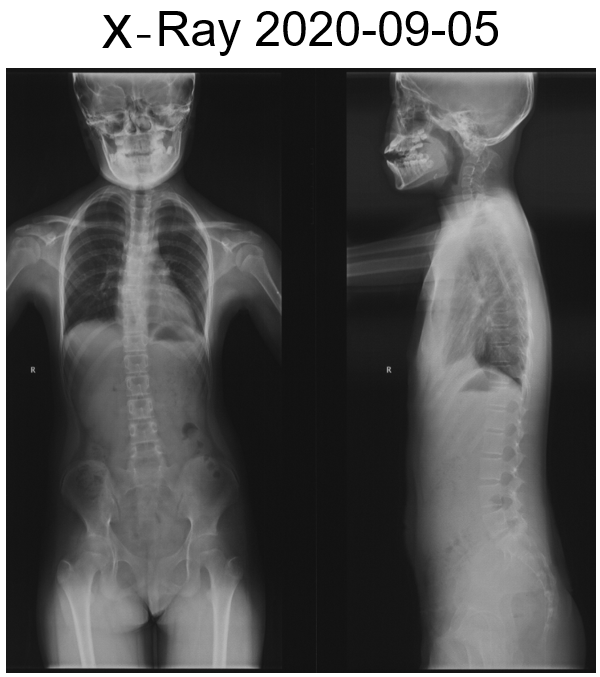

女,13岁,154cm,57kg

• 6个月前病人出现颈部活动受限,3个月前出现左手力弱

影像资料:

• 齿状突小体

• 寰枢椎脱位